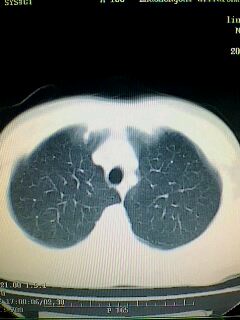

标题: CT28315:咳嗽咳痰咯血半月并胸痛 [打印本页]

标题: CT28315:咳嗽咳痰咯血半月并胸痛

图像资料欠清,建议强化,考虑周围型肺癌。

左肺下叶球形肺炎,建议抗炎治疗后复查